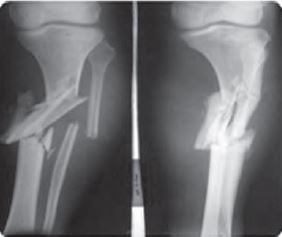

Comminuted:

A fracture in which a bone is broken, splinted or crushed into number of pieces.

Causes - Direct and indirect trauma or violence can be causes for commutated fracture.

Prevention - Maintaining strong bones by eating food that is rich in calcium and regular exercise can help in the prevention of this type of fracture.

Treatment - An X-ray is important for diagnosing of the condition. An open reduction when the bone fragments are jammed-together using surgical nails, wire plates etc. is required for commutated fracture.

Transverse: Transverse fracture is when there is a straight break right across a bone.

Causes - When a large amount of force is transmitted directly ie., perpendicularly to the bone.

Prevention - Physical activity and weight bearing exercises will make the bones stronger and denser. Bones can also be strengthened by eating foods rich in calcium and taking regular exercise.

Treatment - Can be treated at home along with rest and medicine. A back brace (called TSL) or abdominal binder may be prescribed to reduce the pain by limiting motion at the fracture site.

Oblique:

Oblique fracture is one in which the bone breaks diagonally. Causes - This fracture is usually caused by an injury to the bone as the result of a fall, accident or other trauma.

Prevention - Bones can be strengthened by eating food rich in calcium and exercising regularly to help prevent this type of fracture.

Treatment - It depends upon the severity of the crack or break. Anti- inflammatory medication, reduction (Resetting the bone) can also help to some extent.